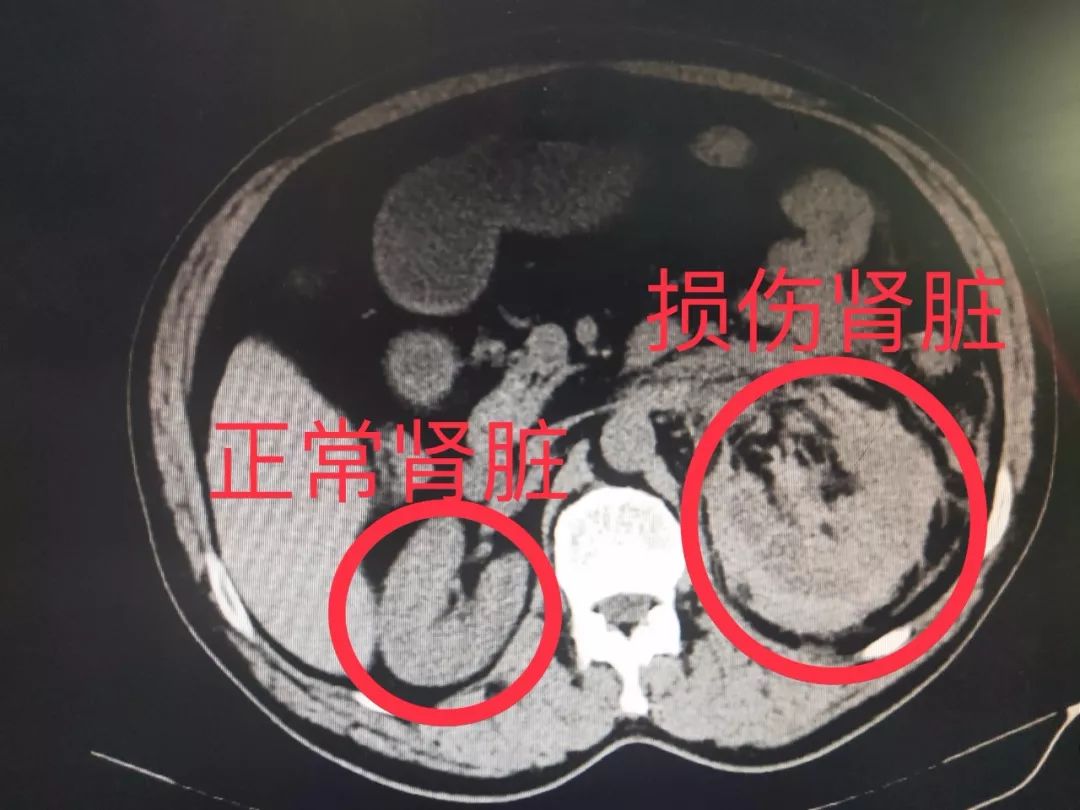

肾损伤分级的ct表现